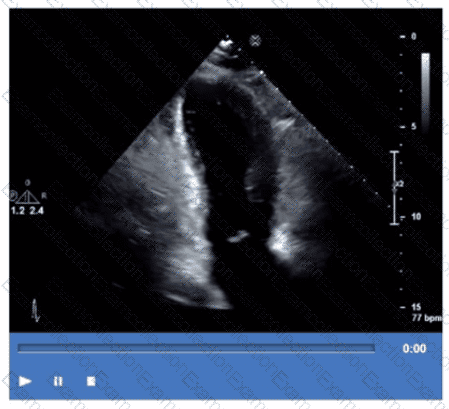

What is the regional wall motion assessment of the two-chamber view displayed in this video?

Which coronary artery territory is associated with the wall motion abnormality demonstrated in this video?